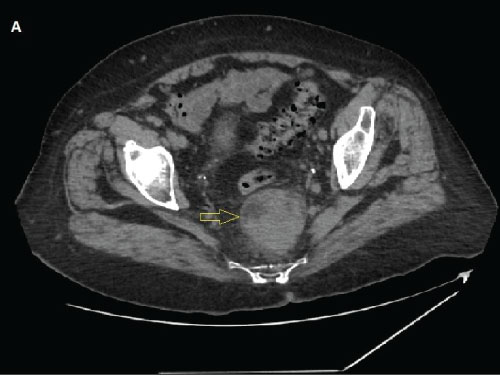

A 76-year-old woman underwent abdominal CT (Figure 1) to explore anemia and fatigue after negative results from upper and lower GI endoscopy. CT scan showed a large heterogeneous pre-sacral mass with a long axis of 60 mm. At digital rectal examination a solid mass was palpable from the posterior rectal wall. At rectal endoscopic ultrasound (EUS), the mass showed an intense hyperechoic in homogeneous echotexture, with hypovascularization and with a soft pattern at elastography (Figure 2). This mass was located in the presacral space without involvement of the rectal wall. The hyperechogenicity of the lesion made it difficult to distinguish its borders from the perirectal fat (Figure 2, white line). An EUS-biopsy was performed using a 25 G Sharkcore needle (Medtronic, Boston, MA). The mass was so hyperechoic that the needle was hardly recognizable inside it. The digital palpation done before the EUS was an adjunctive tool to the EUS guidance to confirm where the needle had to be addressed. The specimen obtained was a microfragment that was collected into formalin and processed as an histological specimen. Immunohistochemistry with MPO and CD61 applied to the histological findings made the diagnosis of extramedullary hematopoiesis (Figure 3).

Figure 1: CT scan of a pre-sacral mass.